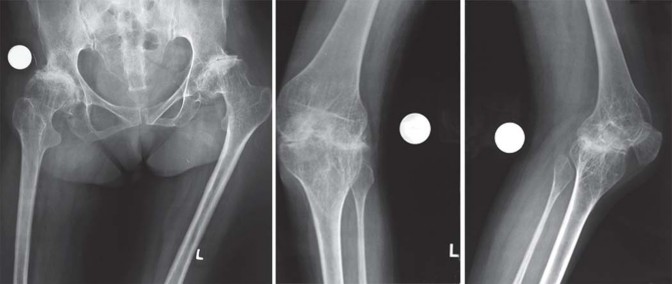

يميل مرضى التهاب المفاصل الروماتويدي اليفعي إلى امتلاك قناة نخاعية فخذية ضيقة جدًا مع عدم توافق بين قطر القناة القريبة والبعيدة. يمكن أن يختلف التجويف الحقي من النوع المشوه (كما يظهر في الشكل 29.1) إلى النوع المنغمس (كما يظهر في الشكل 29.2) أو قد يكون مفصل ورك ملتحم (كما يظهر في الشكل 29.3).

نمط الورك المشوه